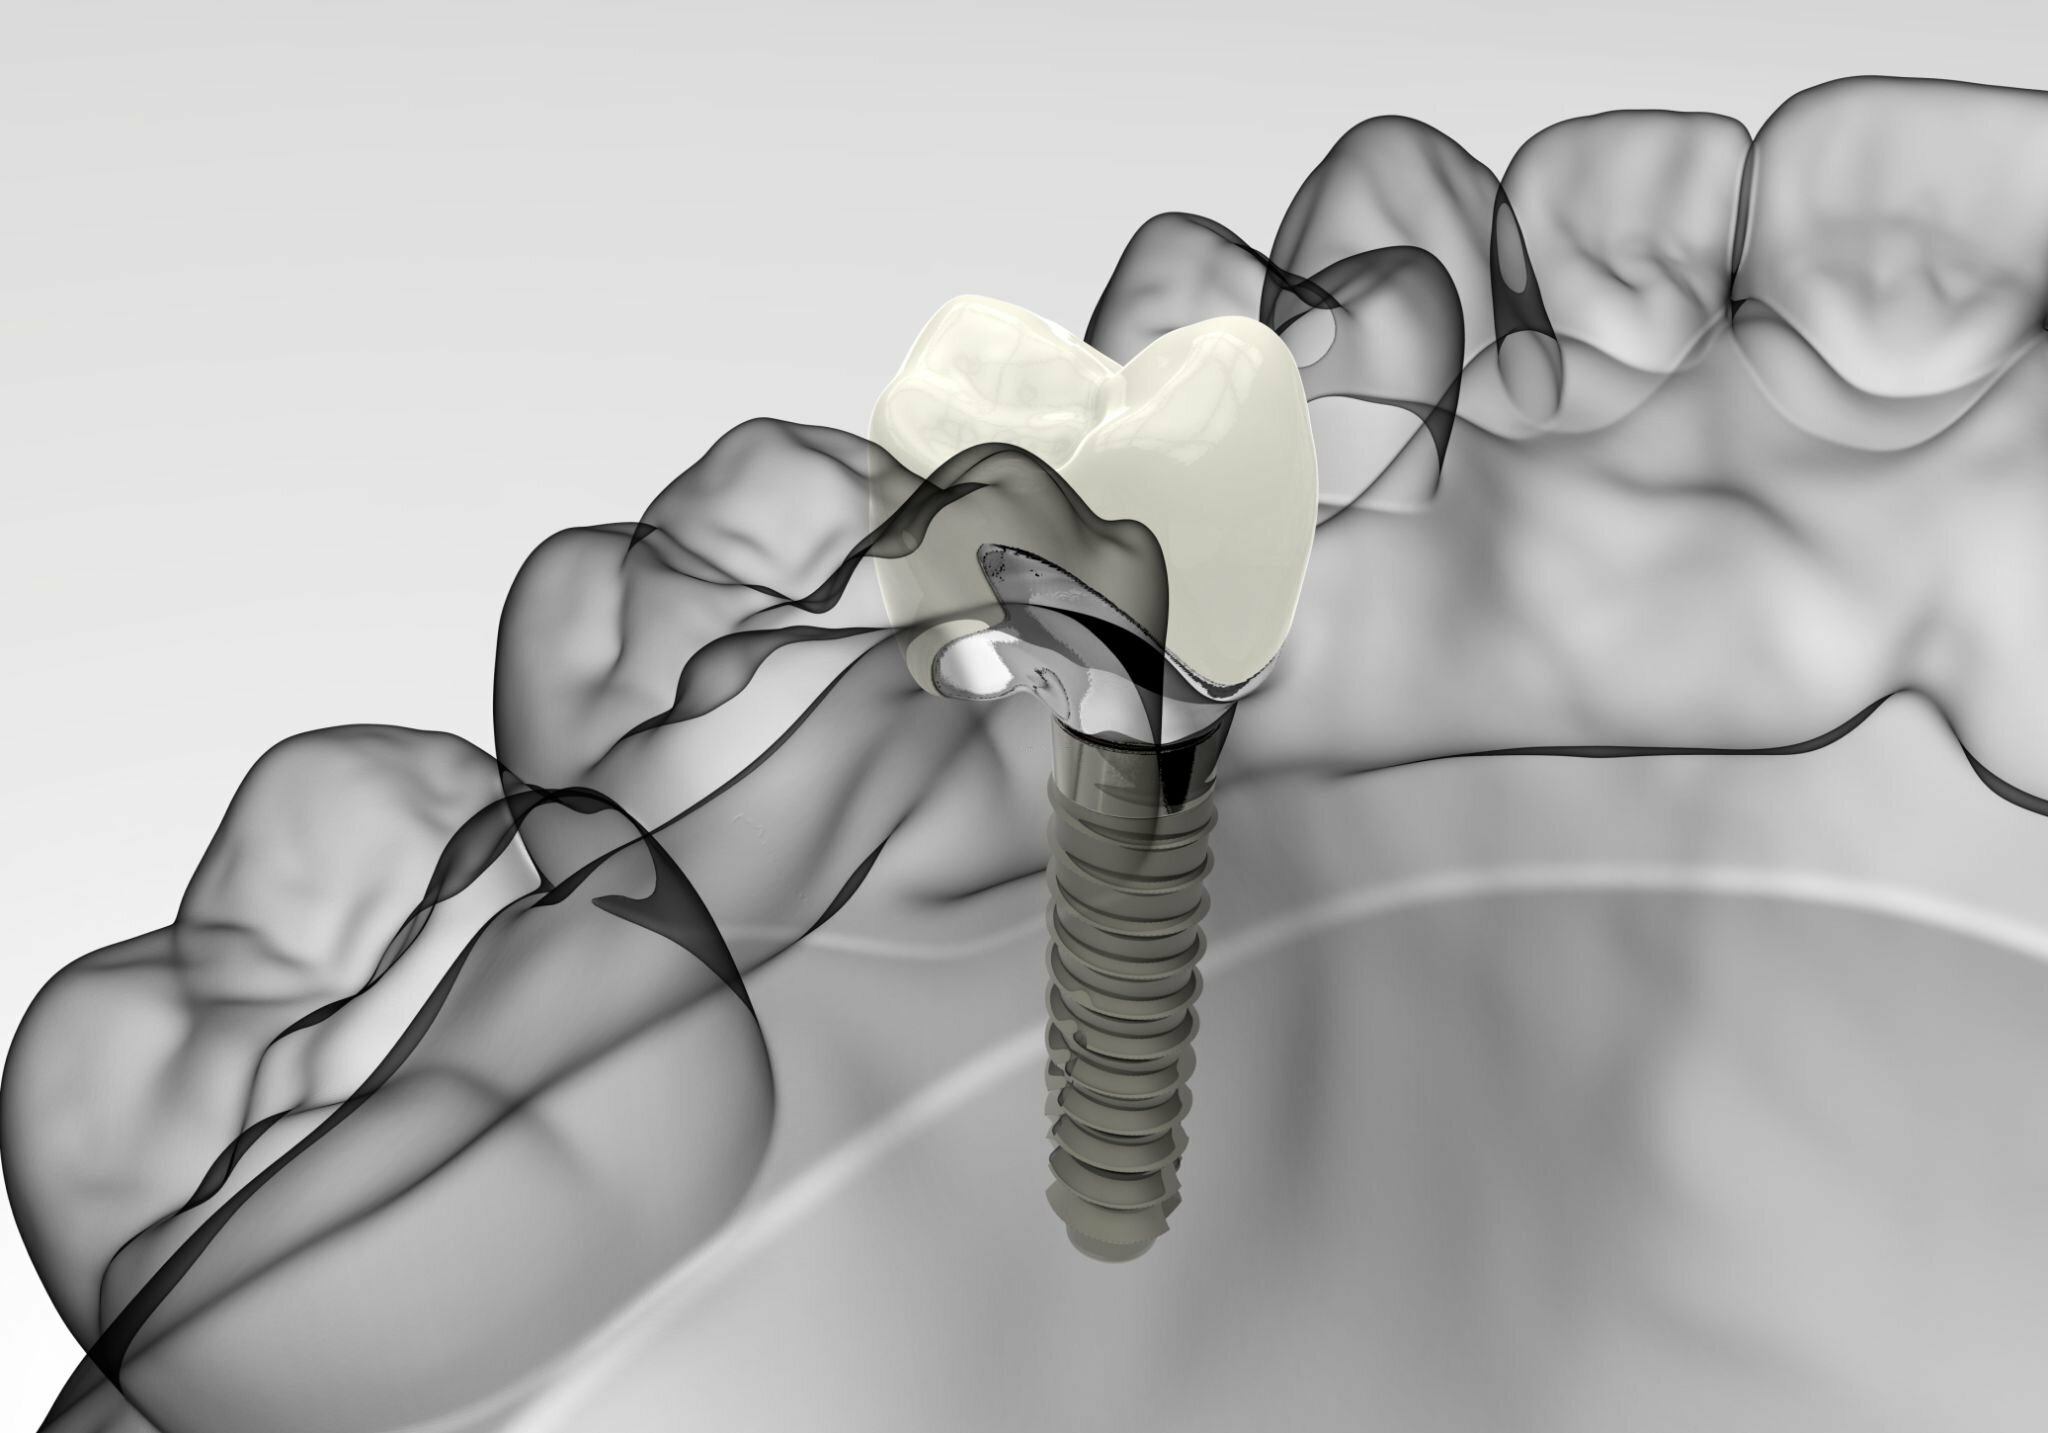

Dental implants are prosthetic teeth designed to mimic your natural tooth. A dental implant primarily comprises three main components, namely:

- Implant: The implant is like a screw that is posted surgically into your jawbone. It substitutes for your tooth root, providing a solid base for the oral appliance.

- Abutment: The abutment is the second core part of an implant. It connects the implant to the crown and is visible over the gumline.

- Crown: The crown is the last part of a dental implant. It sits on the implant to give you the look and feel of a natural tooth.

Dental fixture’s fundamental function and goal is to provide a secure basis for prosthetic teeth. Dental fixtures, as opposed to typical tooth replacement solutions such as bridges or dentures, mirror the structure of natural teeth. They enhance functionality and aesthetics, allowing patients to speak, smile, and eat comfortably.